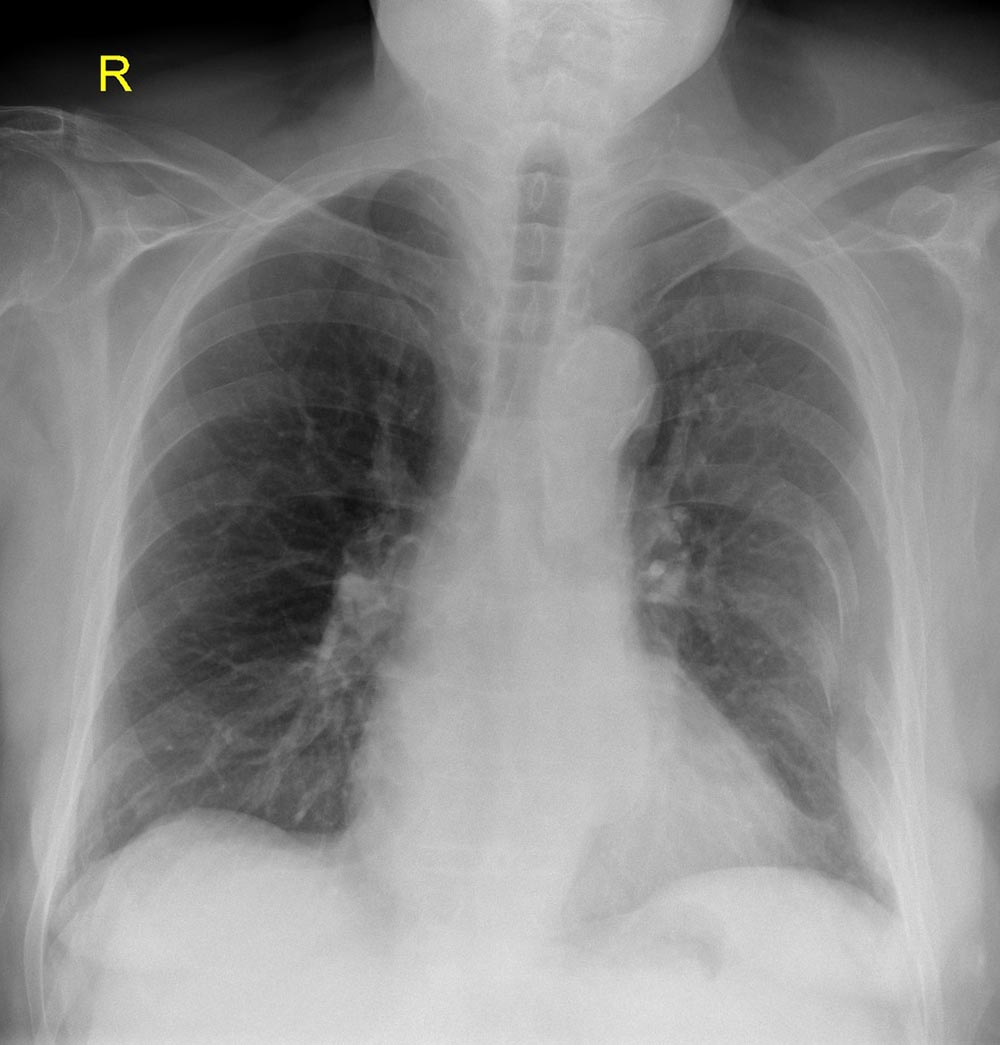

This is a 20 year old male who presents after an MVC. He was the unrestrained driver and was T-boned at approximately 45 mph in an intersection. He complains of pain to his abdomen and chest. He is found to have multiple left sided rib fractures and hemoperitoneum from splenic and liver lacerations. He is hemodynamically stable for EMS but becomes hypotensive and tachycardic in the ED. He should bypass CT and go straight to OR after free fluid found on his EFAST scan. Learners should be able to evaluate a trauma patient as well as perform and correctly interpret EFAST images.